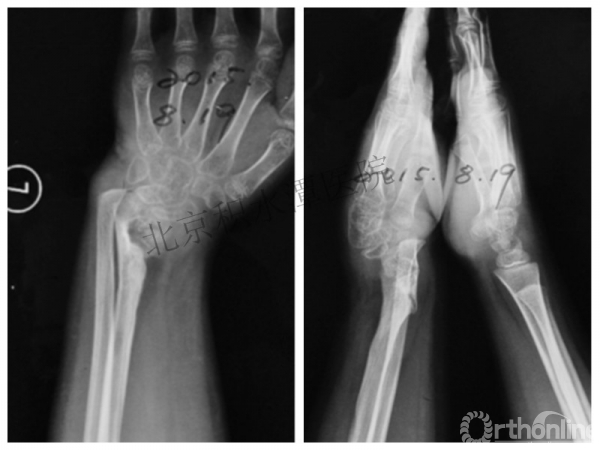

病例分享四

女孩、8岁,桡骨远端骨折

原始损伤

伤后1个月

伤后14个月

病例分享五

女孩、6岁,股骨干骨折

牵引后4周

伤后18月

没有任何外观和功能障碍!相信每位小儿骨科医生都会有很多类似的病例!除非您不承认或者没有认识到塑形!